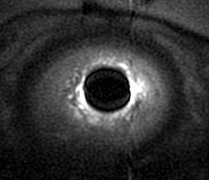

| Pelvic MR images of a continent 32-year-old woman. Imaging parameters were as follows: 3800/99, 6.0-mm section thickness, 2.0-mm section spacing, four signals acquired, 20 x 20-cm field-of-view. R = rectum. Above, axial T2-weighted fast spin-echo image obtained at the level of the upper urethra shows the paraurethral ligament (arrows) extending from the lateral wall of the urethra (U). Below, axial image obtained at the level of the midurethra shows the periurethral ligament (arrows) extending between the medial aspects of the pubococcygeus muscle (arrowheads) and coursing ventrally to the urethra (U). |

| Figures 3a,b. Macura KJ, Genadry RR, Bluemke DA, "MR imaging of the female urethra and supporting ligaments in assessment of urinary incontinence: Spectrum of abnormalities." RadioGraphics 2006; 26:1135-1149. |